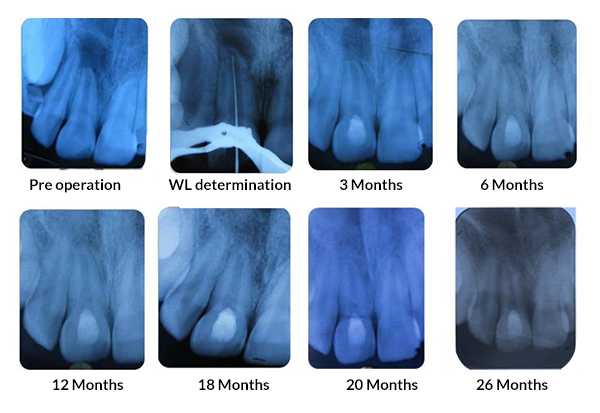

Tanisha Konai -

PRP Mediated REP in 21 with 18 months follow up

Bone healing, Apical PDL formed, Apex Closed, Calcific Bridge formed in 21.

Vitality Positive

PRF Mediated REP in 21 with 26 Months Follow Up

Complete Bony Healing, Apex Closed, Lateral Dentinal Wall Thickened, PDL Apically